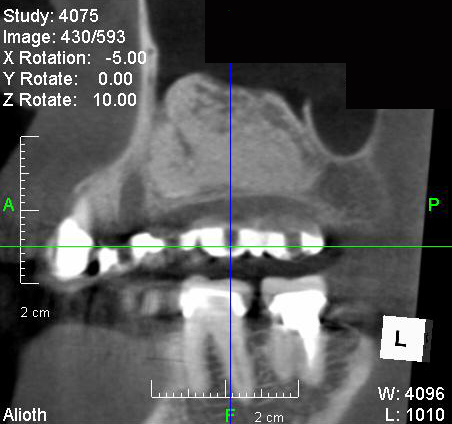

サイナスリフト手術の6ヶ月後のCTです。以前は骨が無く黒く映っていたところに骨が出来て(白く映って)いるのが分かります。

インプラントを埋入し,セラミックスクラウンを被せました。